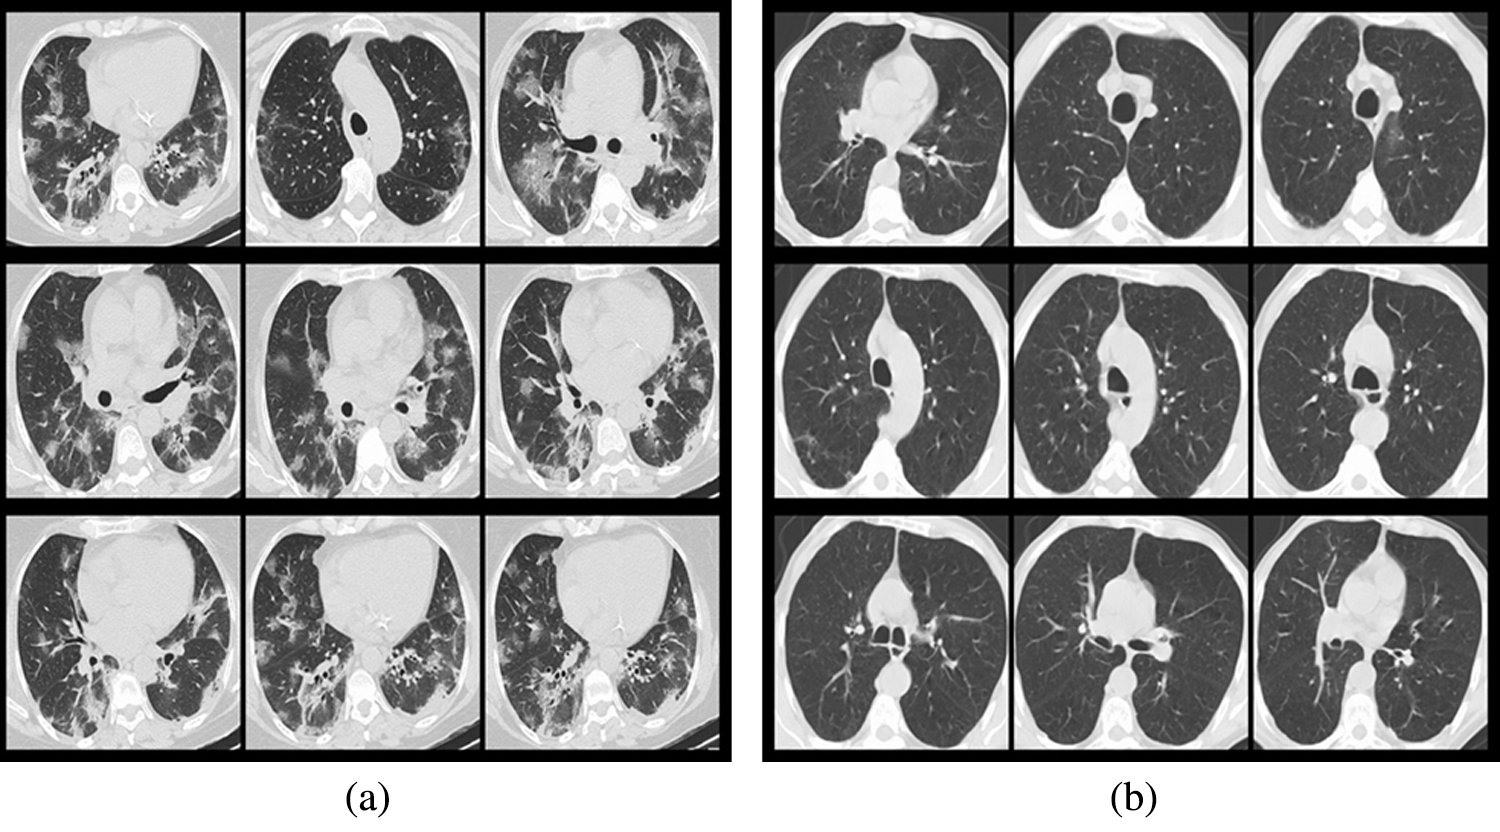

The used data is from the COVID-19 CT image data set available on Kaggle. There are 2,481 chest CT images, 1,252 positive CT images for COVID-19 and 1,229 negative CT images for COVID-19. Fig. 3 shows the samples of COVID-19 positive CT images and COVID-19 negative healthy chest CT images. The size of all the images on the data set was adjusted to 224 × 224 pixels, and the Gaussian blur was used to reduce images noise and improve image quality. According to the ratio of 8:1:1, we divided the data set into three sub data sets, including a training set, a validation set, and a test set, as shown in Tab. 1. The training set is used to train the model for 101 epochs, and then after each epoch, use the validation set to validate the model to ensure the model can successfully complete the training, finally after the training use the test set to verify the performance of the trained model.

Figure 3: Samples from the data set (a) COVID-19 positive samples, (b) COVID-19 negative samples